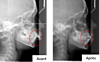

Radiographie avant et après traitement appareil multi-attaches